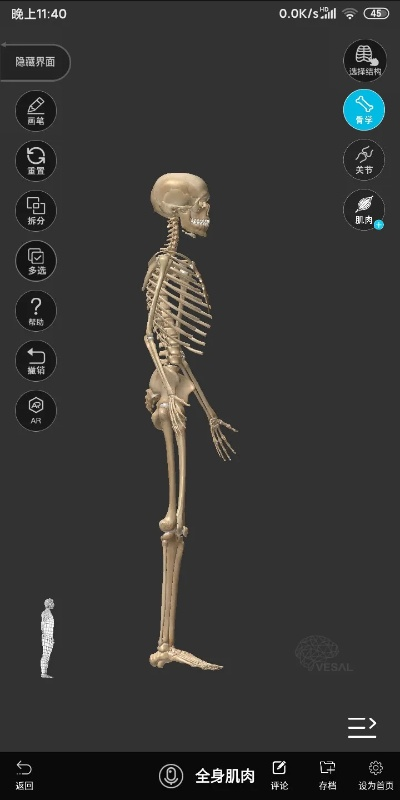

骨骼扫描官方下载和广电新版本,详细数据解释定义|DX版1_v9.914

一、什么是“骨骼扫描官方下载和广电新版本,详细数据解释定义_DX版1_v9.914”?答:“骨骼扫描官方下载和广电新版本,详细数据解释定义_DX版1_v9.914”是一款结合骨骼扫描技术与广电新版本的软件,用于对骨骼...

骨骼扫描官方下载和广电新版本,数据设计支持计划|冒险版_v3.652

初始经典版本时间回溯到我们的软件刚刚诞生的时代,那时的骨骼扫描官方下载和广电新版本数据设计支持计划冒险版还处于初始的经典版本,这个版本主要为用户提供了基础的骨骼扫描功能,以及广电行业的基础数据管理,这是我们的起点,为...